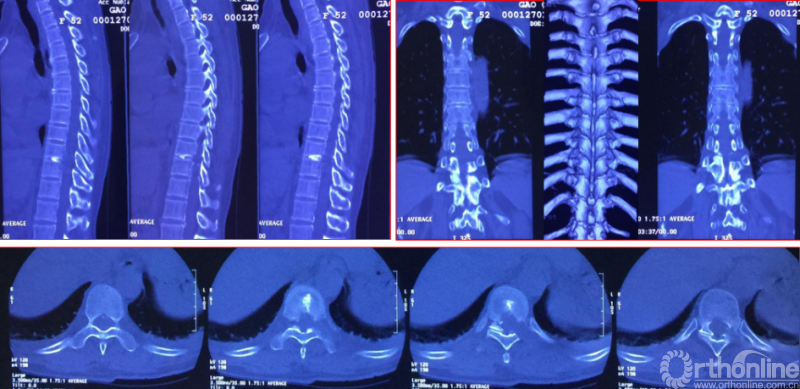

影像学资料

术中资料

同一侧一次两个节段减压,择期对侧进行两个节段减压,两侧腹侧减压范围可达到硬膜囊360度环形减压效果。术后复查硬膜囊环形减压效果。关节突关节破坏较多,需长期佩戴支具固定,保证术后脊柱稳定性。

术后复查资料